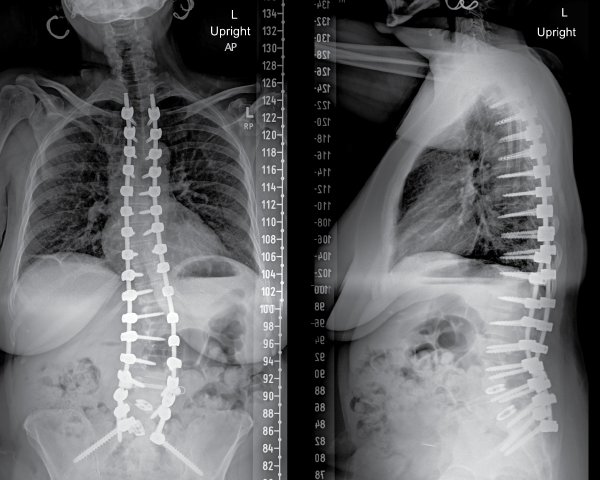

Cynthia’s surgery was extensive, lasting eight hours and involving a long incision down her back. Dr. Zussman used advanced imaging techniques to guide the placement of 17 levels of screws with precision. He removed damaged discs and relieved pressure from pinched nerves. The screws were then connected by long, strong rods to realign her spine, restoring its shape and function.

Post-operative X-rays show Cynthia standing up straight. The screws, rods and spacers help to brace her skeleton internally and maintain her posture.